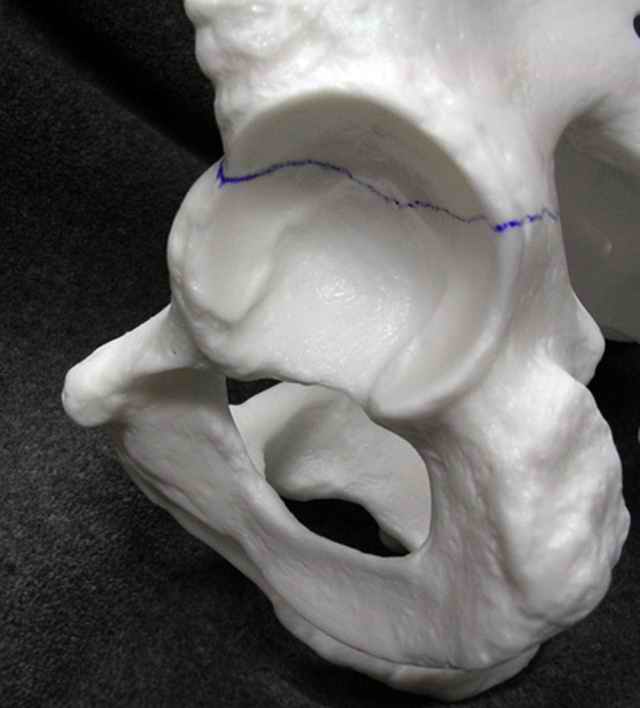

You can adjust the quadrilateral surface contact point as needed to get the fracture to reduce...we plan this based on the fracture orientation on the preop CT scan images...the clamp should be balanced to avoid over compressing one portion and distracting the other limb. Go back to and you¹ll see on the injury CT where the clamp tines need to be.

Prone

Here's a pic from the foot of the bed and you can see the clamp in the wound and the knee is extended so he must've had a tight rectus. The C-arm is rolled back to an obturator oblique image to reveal the anterior column...we put a slight outlet tilt to combine the images and give a better view of the anterior column...we can see the posterior column limb reduction in the wound, we can palpate the quadrilateral surface limb, and the image demonstrates the anterior column portion...you can adjust the tilt and rotation to image tangentially to the fracture plane if you'd like. We've inserted a 2mm K wire to site the starting point and aim/orientation for the drill and screw